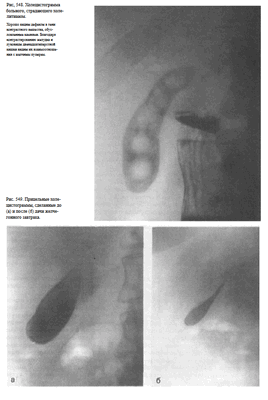

Информативность снимке. На латерограмме отображаются преимущественно правая половина живота и расположенные здесь органы. Особенно отчетливо при этом виден свободный газ в брюшной полости (рис. 543).

Рекомендуется делать 4 снимка: два — в прямой передней проекции в положении больного стоя (один — без компрессии, второй — с компрессией), третий снимок также в положении больного стоя в левой косой проекции и последний — в положении больного лежа на спине. Первые три снимка обычно выполняют за экраном рентгеновского аппарата под контролем просвечивания, последний — на снимочном столе (рис. 546). Кассету размером 24X30 см устанавливают под правую половину живота с таким расчетом, чтобы центр ее находился на середине расстояния между нижними ребрами и гребнем правой подвздошной кости.

У здоровых людей на холецистограммах определяется интенсивная однородная тень желчного пузыря с четкими контурами (рис. 547).

При калькулезных холециститах тень пузыря менее интенсивна, в проекции пузыря определяются дефекты наполнения, образованные камнями(рис. 548).

Для оценки сократительной и эвакуационной функции желчного пузыря после выполнения снимков (при наличии на них отображения тени желчного пузыря) больному дают желчегонный завтрак (сырые желтки, сливочное масло, сорбит) и спустя 20 и 50 мин делают прицельные снимки (рис. 549).